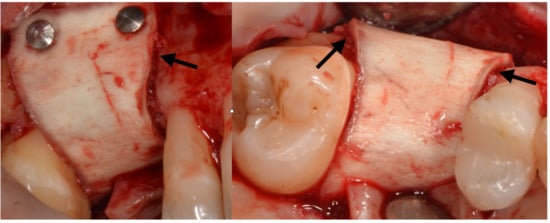

The site of 12 presented a very thin but visible buccal plate, while 11 had most of the buccal coronal aspect of the implant exposed. Some small holes were drilled into the buccal plate to produce some bleeding and with cells from the marrow spaces, while the area was augmented with a mix of autogenous bone scraped from the ramus and a collagenated xenograft. A bone lamina was cut and shaped in order to cover the graft and produce some horizontal and vertical augmentation of the area (Figure 15). We can see that some bone loss to the distal of 21 was also evident. Two pins were placed to the buccal apical aspect of the lamina to keep it firmly in place.

Figure 15.

The bone lamina stabilized to protect the two implants.

Six months after surgery the area looked healthy and the dimensions restored (Figure 16).

Figure 16.

Healing at 6 months, the arrows point to the step created by the lamina.

At second stage surgery, a mini-flap was prepared in order to connect healing abutment and protect the papilla; the bone lamina was still in place and it was necessary to drill through it in order to access the implant’s heads (Figure 17 and Figure 18).

Figure 17.

The bone lamina integrated.

Figure 18.

Progression of the case.